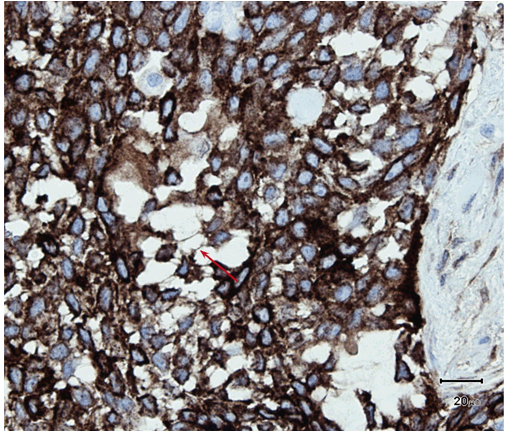

A 61-year-old male was presented to his dermatologist with a solitary nodular dermal lesion on his lower back (1.5x2 cm). He was otherwise well and was taking no medication. A biopsy demonstrated squamous cell carcinoma (SCC), and the patient was referred to our service for complete local excision. On follow-up, a month later, the patient presented with hemoptysis, hip-, and abdominal pain. Magnetic resonance imaging (MRI) scan confirmed the presence of lung, liver, and bone multiple metastases. As planned, a complete local excision with a 7.5 mm margin was performed. Histology confirmed the diagnosis of SCC. Furthermore, the patient had developed another solitary dermal lesion localized to the chin. This lesion was not present only a month prior during the visit to the dermatologist. A biopsy from this lesion also demonstrated SCC. The specimens from the back and chin were later studied with immunohistochemistry. The morphology suggested SC, with the tumor showing a solid arrangement of cells with nuclear pleomorphism, atypical mitosis, basophilic and vacuolated cytoplasm (Figure 1) and (Figure 2). In addition, immunohistochemistry showed tumor positive for epithelial marker Ber-EP4, pancytokeratin (Kl1) and epithelial membrane antigen (EMA) (Figure 3). Reactivity for p53 and proliferating cell nuclear antigen (Ki67) was high, showing 80–90% hot spots labeling of the tumor cells (Figure 4) and (Figure 5). Immunoreactivity levels of cancer protein p53 and Ki67 above 10 and 25% indicated a poor prognosis (Figure 6). It was then concluded that the correct diagnosis of both tumors was in fact SC and not SCC.

Figure 3: Arrow showing EMA reactivity also in the thin vesicular wall in the cytoplasm (H&E stain, x400).